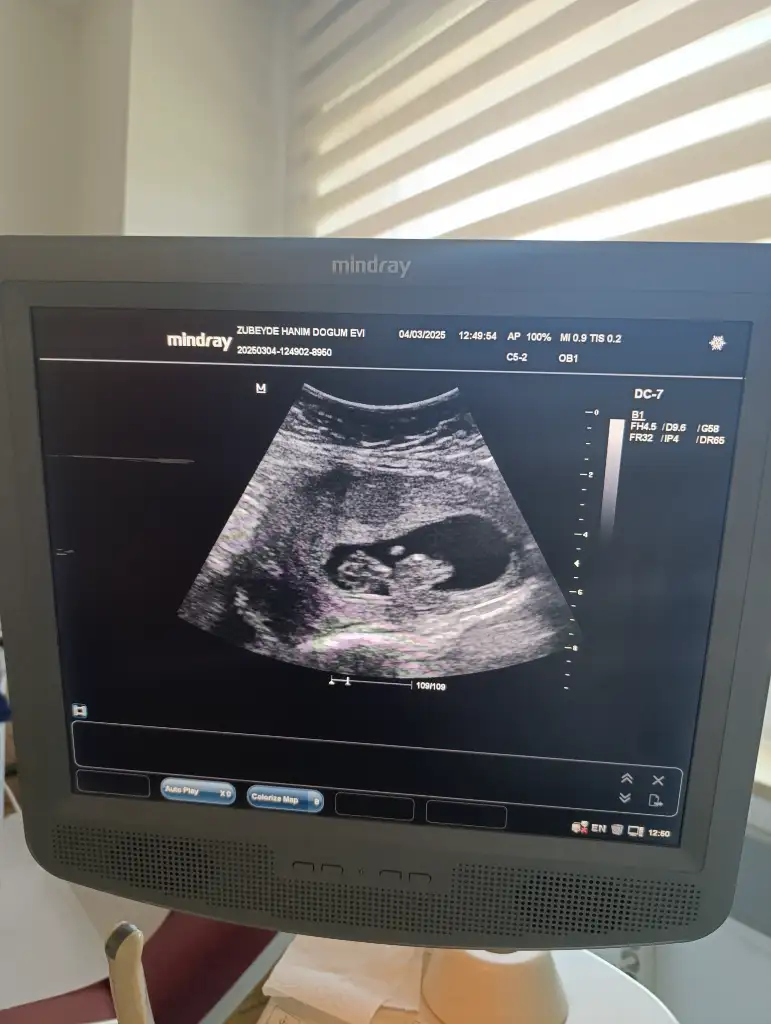

Merak içerisindeyim 2 gün sonra ikili taramamiz var ama ben siz güzel annelerede sormak istedim cinsiyeti ne olabilir bebişimin

O üste duran yuvarlak şey yolk kesesi mi. Halen daha kaybolmadı mı ? Eğer yolk kesesi ise tektaş gibi üstünde kız diyorum. Ama anladığımdan değil . Sağlıklı olsun da sizin olsun inşallah annesi

Ben hiç anlamıyorum ki yolk kesesi nedir onu bile bilmiyorum teşekkür ederim bu arada